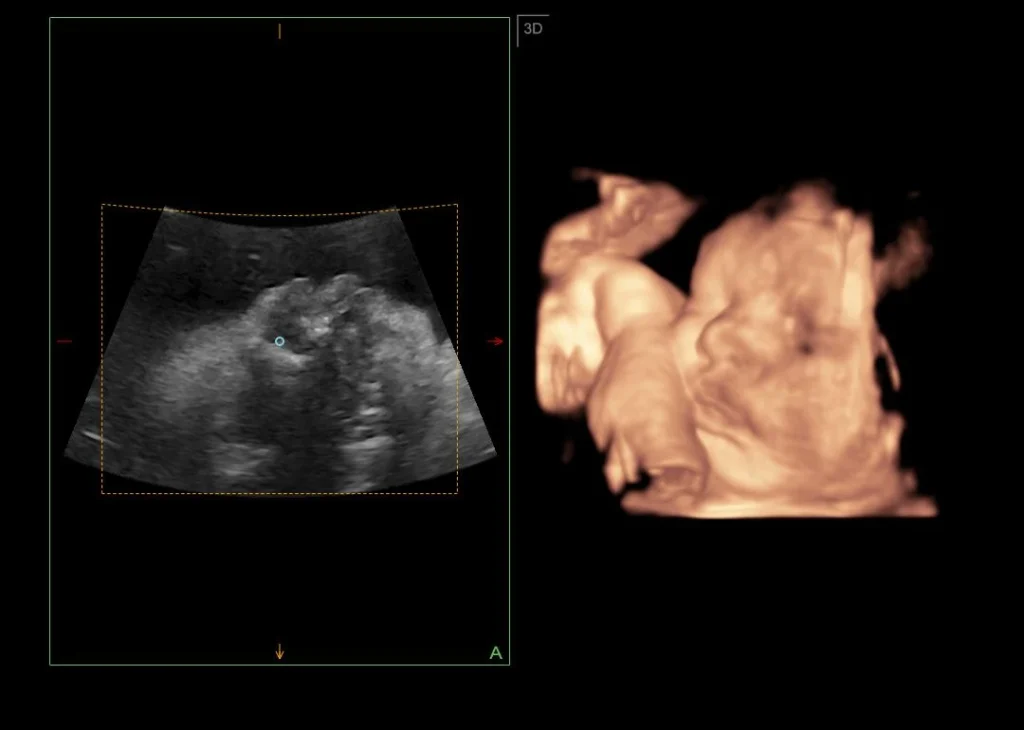

Salah satu produk unggulan Grin adalah USG 4D, yang menjadi pusat perhatian dalam kegiatan ini. Alat ini memiliki keunggulan berupa resolusi gambar yang tinggi serta kemampuan menampilkan citra janin secara real-time dalam format 3D/4D dengan visual yang sangat jelas. Grin USG 4D juga dilengkapi dengan multi probe yang dapat digunakan bukan hanya untuk mengecek kandungan, tetapi juga abdomen dan kardiologi. Grin USG 4D telah melalui serangkaian uji coba di beberapa rumah sakit serta digunakan oleh sejumlah dokter spesialis kandungan, dan terbukti memberikan hasil yang akurat dan stabil. Meski dikembangkan secara lokal, kualitas pencitraannya dinilai sebanding dengan produk luar, bahkan hadir dengan keunggulan berupa antarmuka yang lebih sederhana dan panel kontrol yang ramah pengguna serta touchscreen.